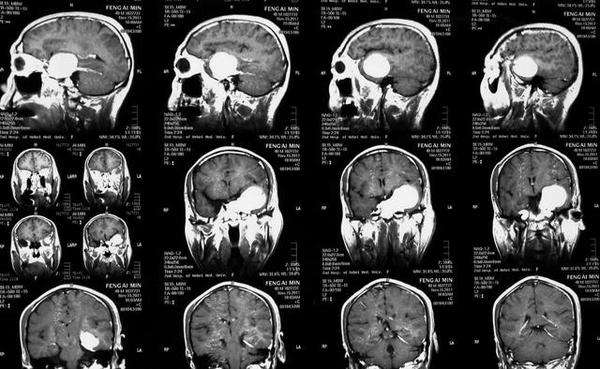

MRI表现:病灶中相对脑实质来说T WI上呈等信号,或稍低信号,信号均匀,少数内部见小片高信号。T WI及T 一FLAIR上均为明显高信号。CSHAs的血供丰富及解剖结构较复杂,术前误诊率和术后致残率均较高,掌握其CT、MR及DSA等各种影像学检查方面的特征性表现,可提高术前定位及定性诊断的准确率,对于临床治疗方案的制定、确定手术入路以及减少手术致残及致死率有着十分重要的意义。

有学者认为海绵窦海绵状血管瘤与雌激素、孕激素和促性腺激素的水平有关 。而Ohata等则认为这是颅内高血流状态和动脉收缩压升高所致。有文献报道部分患者有腺垂体功能减退的症状,与肿瘤向鞍内生长有关。海绵窦海绵状血管瘤的影像学特点为同时累及鞍旁和鞍内的单发大肿块,呈哑铃状,密度多均匀而少出血和钙化,其在CT扫描时呈等或稍高密度,瘤内常无钙化,可侵蚀颅骨,但一般不伴骨质增生。MRI扫描时T wI明显高信号和显著均质强化是其重要的诊断依据 ” 。